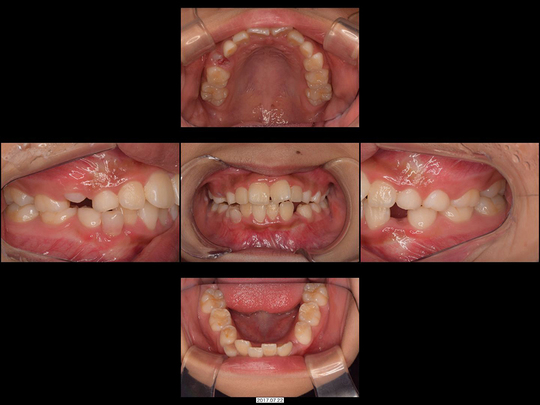

Sさん 開始時8歳 女性

矯正前

画像をクリックで拡大

矯正後

上下の前歯がガタガタでお悩みのお子さんです。

スタート時は1期治療前半の時期で、精査の結果、あごの骨年齢も実年齢と変わらないことが分かりました。そのためワイヤー矯正なし、通常通り固定式拡大装置を用いた非抜歯矯正で対応しました。

治療の期間・回数

36か月、36回

​費用

576,400円